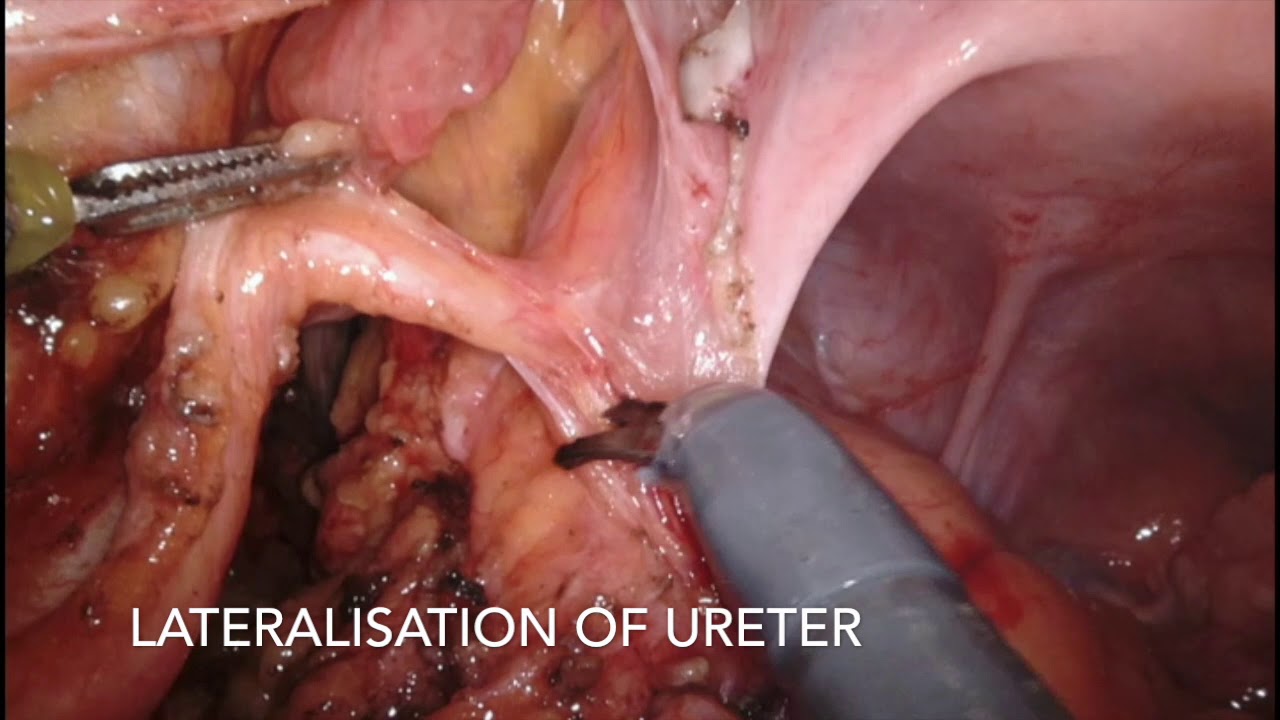

Robotic Enucleation of Renal Hilar Tumour

Oncology, Robotics, Urology ';

Robotic Enucleation of Renal Hilar Tumour

Robotics, Urology ';